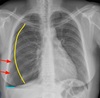

1

Pneumotórax